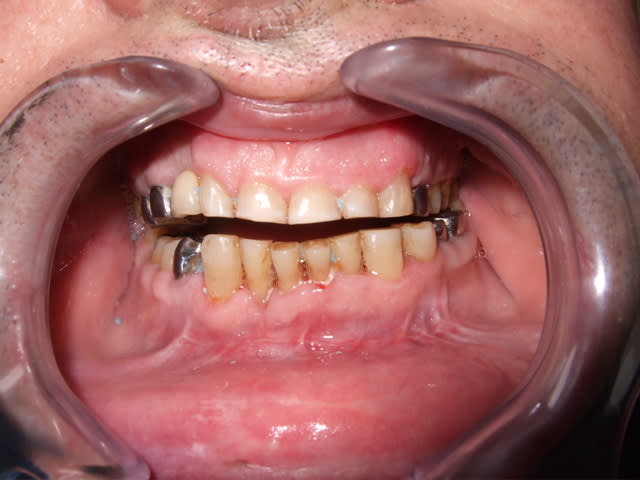

- retrait des ligatures et chirurgien septique me laisse un courrier en me demandant de meuler les molaires pour rattraper le décalage.

Bon je fais une petite mesure rapide : 38 = 1,5mm de hauteur coronaire, et béance de près de 4mm au maximum

c'est quand meme scandaleux d'avoir opere cet homme de la sorte en ne connaissant meme pas les principes de bases de ce type de chirurgie.

Ben comme j'ai une occlusion de frasaco, je m'attendais pas a grand chose; mais le chir est une merde sasn nom

Il est absolument impensable de laisser quelqu'un comme cela et compenser par de la prothèse.

sans etre A CHEVAL sur les principes d occlusion je pense de meme qu il faut repositionner meme avec 2 semaines d atelles totales

perso ce qui m embete c est la double frature des condyles sans plaques ni bloquages ...